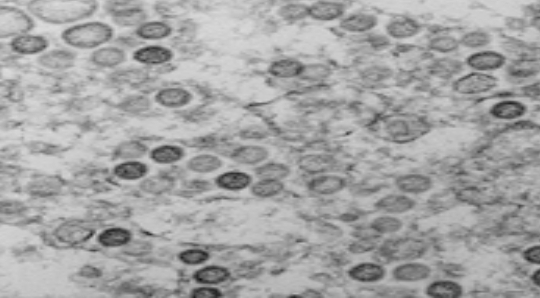

신종 코로나바이러스 감염된 일본인 첫번째 사망자 나와

일본 외무성은 중국에 체류하는 일본인 가운데 신종 코로나바이러스감염증 환자로 추정되는 사망자가 처음으로 나왔다고 밝혔다.일본 외무성은 8일 신종코로나 발원지인 중국 후베이(湖北)성 우한(武漢)에서 폐렴 증세로 입원 치료를 받던 60대의 자국민 남성이 사망했다고 발표했다.일본 외무성은 개인정보 보호를 이유...- 알쓸신잡

일본 외무성은 중국에 체류하는 일본인 가운데 신종 코로나바이러스감염증 환자로 추정되는 사망자가 처음으로 나왔다고 밝혔다.일본 외무성은 8일 신종코로나 발원지인 중국 후베이(湖北)성 우한(武漢)에서 폐렴 증세로 입원 치료를 받던 60대의 자국민 남성이 사망했다고 발표했다.일본 외무성은 개인정보 보호를 이유로 자세한 신원이나 사망일 등을 공개하지는 않았다.이 남성이 신종코로나 감염으로 숨진 것으로 판명되면 ...- 알쓸신잡